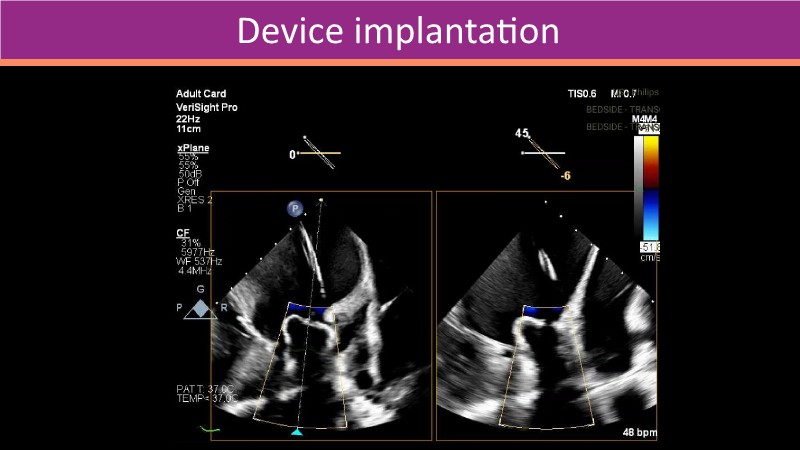

This PCR London Valves 2025 session explores how 3D TEE, 3D intracardiac echocardiography (ICE), and DeviceGuide technology sharpen procedural accuracy, strengthen operator confidence, and streamline decision-making in real time.

The session also includes detailed case analyses—such as Mitral TEER and LAA closure—and dual perspectives from both proceduralists and imagers.